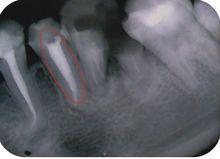

效果對比

側方加壓效果VS熱牙膠充填

熱牙膠充填